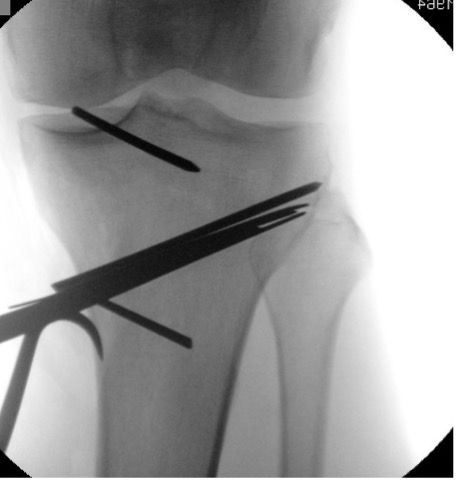

Determination of the osteotomy plane with 2 K-wires.

A first K-wire (3.0) is inserted under image intensifier monitoring from the dorsal superior margin of the pes anserinus to the superior margin of the tibiofibular joint. In order to be able to expose the tibiofibular joint, the knee is brought to 30° IR. The intraosseous length of the K-wire is measured at the same time.

A second K-wire (3.0) is positioned further anterior under image intensifier control so that the two wires are exactly superimposed. This requires that the lateral tibia plateau in the AP image only shows one line. Thus, the osteotomy plane matches the natural tibia slope in the lateral view (Fig. 5a). Thereafter, the length of the two wires is determined (ventrally usually about 10 mm shorter than dorsally).

Placement of parallel K-wires for intraoperative control of the tibial slope and rotation

Now a third K-wire (3.0) is introduced centrally in the proximal tibia with neutral rotation (patella in the center). At the same time, the knee should be flexed under image intensifier control so that the lateral tibia plateau appears as one line. This K-wire now has to appear in the image intensifier as a dot and is thus parallel to the tibial slope (Fig. 5 b).

After predrilling, a fourth K-wire (3.0) is inserted parallel to the third K-wire distal to the osteotomy surface on the anterior tibia (Fig. 5 b). Together with the third K-wire this fourth K-wire permits control of tibial slope and rotation change during the operation.